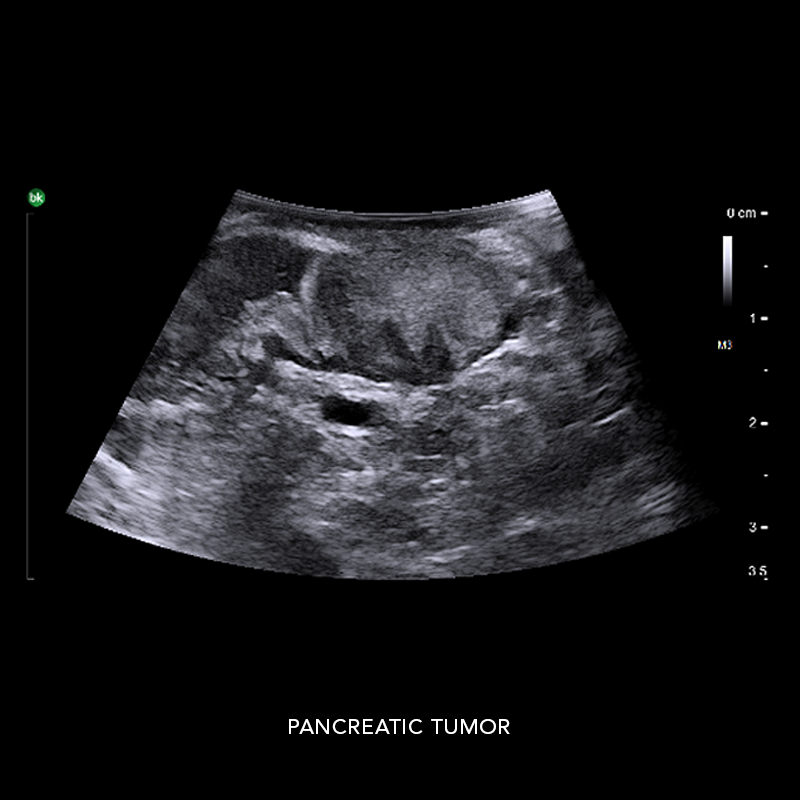

Hepatobiliary Surgery

Reach critical information and compensate for no haptic feedback with active imaging

Intraoperative ultrasound can assist in identifying 10-25% more hepatic lesions than with preoperative imaging alone.* Use intraoperative ultrasound (iUS) to support liver resections, distal pancreatectomies, and more. iUS helps to adapt surgical plans, assess progress, and perform organ-sparing procedures. The active imaging provides real-time information to understand complex anatomical variations, tumor locations, and invasion of vasculature, as well as help define an adequate margin of rection. At the end of the procedure, active imaging can provide certainty and help confirm results.